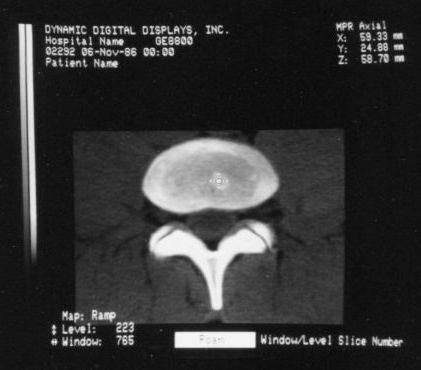

Here are typical examples of VoxelQ displays. These are mostly only windows, not the full screen which is more along the lines of the last block of AcQSim photos.

VoxelQ Multiplanar Reformatting (Axial, Saggital, Coronal, Curved)

The first workstation to be seriously marketed was Voxelscope II (VS2) which had greatly enhanced volume memory and higher display resolution. Unfortunately, that came at a cost and it, and all its successors never even came close to achieving the true video-rate real-time performance of the VPP, which would have required the massively parallel technology in the Patent. But even very early on, VS2 had somewhat real software with a Graphical User Interface (GUI) and enough functions to be credible, at least for demos including instantaneous Multi-Planar Reformatting (MPR) which could display a slice though the object at any depth aligned with one of the principal axes (axial, saggital, or coronal) or at an arbitrary angle, as well as real-time (fraction of a second, but not video rate) 3-D shaded surface with density selection and slicing. A Motorola 68000-based VME bus single board computer replaced the PDP-11 or VAX (sorry DEC) and implemented the high level control and Graphical User Interface (GUI), ran the file system, and interfaced to the outside world.

The pair of video monitors was the focus of the booth, displaying sequences of skulls and such from real CT datasets like those in the above photos being rotated, sliced, and diced at reasonably rapid update rates. The instructions for performing the operations were captured and recorded but the actual voxel processing was done in real-time based on the stored program. Thus, no one needed to be constantly spinning the trackball, though that could have been arranged upon request. :) The monitors were up high so visitors couldn't get close enough to see how poor the resolution was. :( :) It is believed that VS1 had a microcode-based pipeline running at 10 MHz so that a 128-cube (2,097,152 voxels) could be manipulated at around 5 images per second. The display was 256x256 pixels on a 60 Hz non-interlaced display - double that of VPP. But object space could be configured to be any arbitrary rectangular prism as long as all the data fit into the voxel processor's memory. The photos, above, are typical of the displays at RSNA.